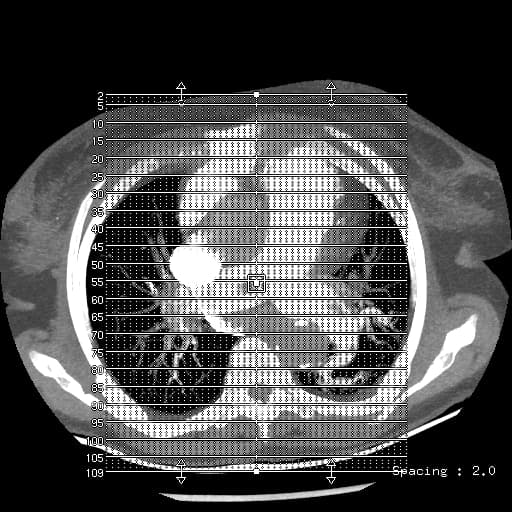

Coronal Lung PBV (CTPA)

Tình trạng sau phẫu thuật cắt thùy trên phổi phải. Hình ảnh xoáy vặn các động mạch thùy giữa phổi phải kèm theo tắc nghẽn tĩnh mạch và phế quản thùy giữa tại rốn phổi. Thùy giữa phổi phải xẹp một phần với đông đặc ngoại vi, thay đổi dạng kính mờ và giảm ngấm thuốc phù hợp với nhồi máu. Phối hợp với tràn khí màng phổi lượng ít ở đỉnh phổi phải và tràn dịch màng phổi lượng vừa bên phải. Bản đồ Iod cho thấy giảm tưới máu thùy giữa phổi phải. Các dấu hiệu phù hợp với xoắn thùy giữa phổi phải.